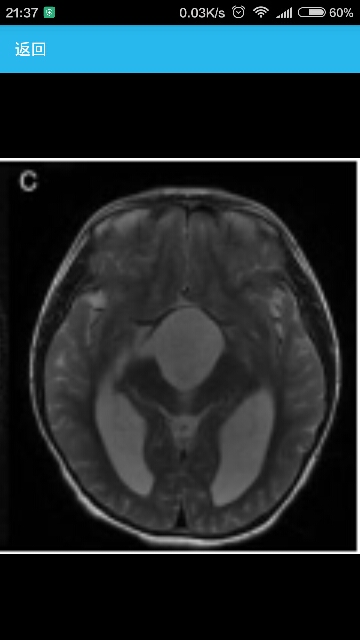

辅助检查头颅MRI可见一51*52*52mm大小,边界清楚的蝶鞍上蛛网膜囊肿,侵入第三脑室。室间孔在脑桥前池和双侧蝶鞍旁区域被堵塞,脑室扩大(图1)。T2像未见进入室管膜的脑脊液,提示为慢性代偿性脑室扩大。

该蛛网膜囊肿在脑垂体漏斗部及视神经交叉部占位效应明显。考虑到压迫脑垂体漏斗部及视神经交叉部的严重程度,以及引起的性早熟症状,予内窥镜囊肿开窗切除术,术后未出现并发症。